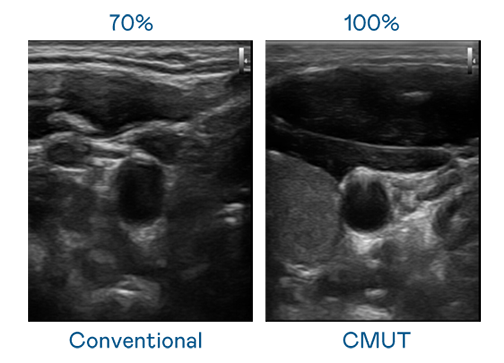

CMUT 技术是一种用电容式微机电元件来产生超音波讯号的技术。与传统 PZT 压电式技术相比,CMUT 频宽增加 30%,更宽频的超音波讯号让影像解析度大幅提升,是实现高影像品质医疗超音波扫描、促进精准医疗发展的关键技术。

超音波影像的解析度高低,首先取决于探头能发出的讯号频宽。long8-龙8(龙八国际)唯一官方网站 CMUT 可提供高清晰的超音波讯号,提供高频宽、高灵敏度、影像纹理细节更高的超音波影像,协助医护人员缩短影像判读时间及利用精准的医疗影像进行诊断。